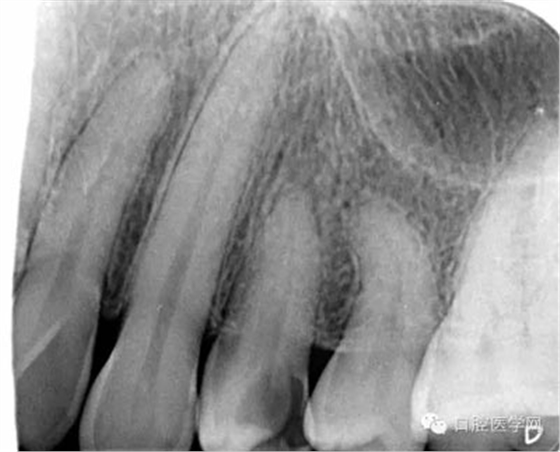

第一步:拍攝X線片,觀察髓腔形態(tài)以及根管走向,疑似根管長度較短且彎曲。